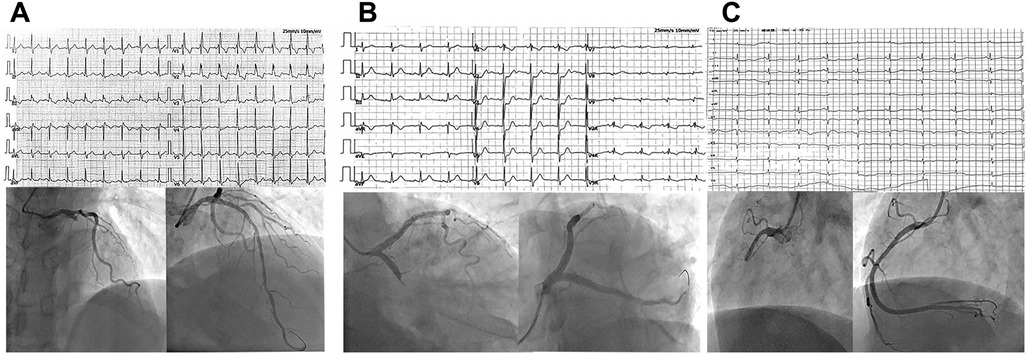

Objective: To investigate the clinical characteristics of NSTE-ACS patients with totally occluded infarct-related artery (IRA-TOCA) and validate the novel SAVE risk score for early identification. Methods: This retrospective study analyzed 185 consecutive NSTEMI patients undergoing coronary angiography, stratified into IRA-TOCA (n=61) and IRA-NTOCA (n=124) groups. Baseline characteristics, angiographic findings, and post-PCI biomarkers were compared. Risk stratification was performed using GRACE and SAVE scores. Results: IRA-TOCA patients exhibited significantly higher post-PCI cTnI levels (8.3 vs 3.34 ng/mL, P=0.001), indicating more severe myocardial injury. Multivariable analysis identified IRA-TOCA (OR 3.64, 95%CI 1.77-7.49) and elevated BNP (OR 1.001, 95%CI 1.000-1.002) as independent predictors of cTnI elevation. The SAVE score demonstrated superior discriminatory ability (sensitivity 73.8%, specificity 54.8%; P<0.001) compared to GRACE score(P=0.384). Left circumflex artery was the most common occlusion site (47.5%). Conclusion: IRA-TOCA represents a high-risk NSTE-ACS subtype with distinct biomarker profiles. The SAVE score enables early identification, potentially guiding timely revascularization.